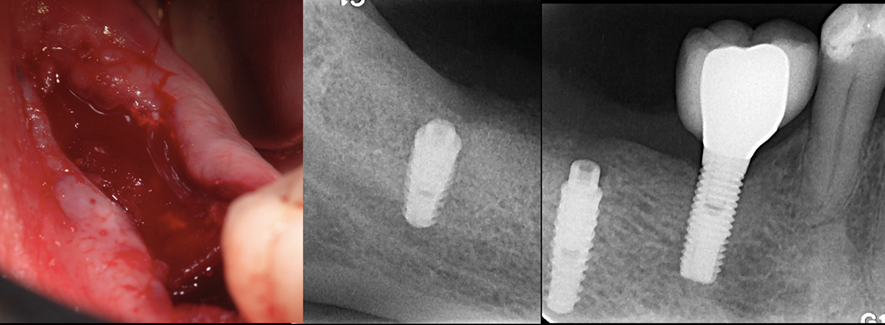

Figura 2 – Imagens clínica e radiográfica da cirurgia de colocação de dois implantes Cone Morse Maestro (Implacil Osstem – São Paulo – Brasil) e a regeneração óssea guiada com hidroxiapatita bovina mais colágeno tipo 1 (Extra Graft – Implacil Osstem – São Paulo – Brasil), recobertos por uma membrana de colágeno.